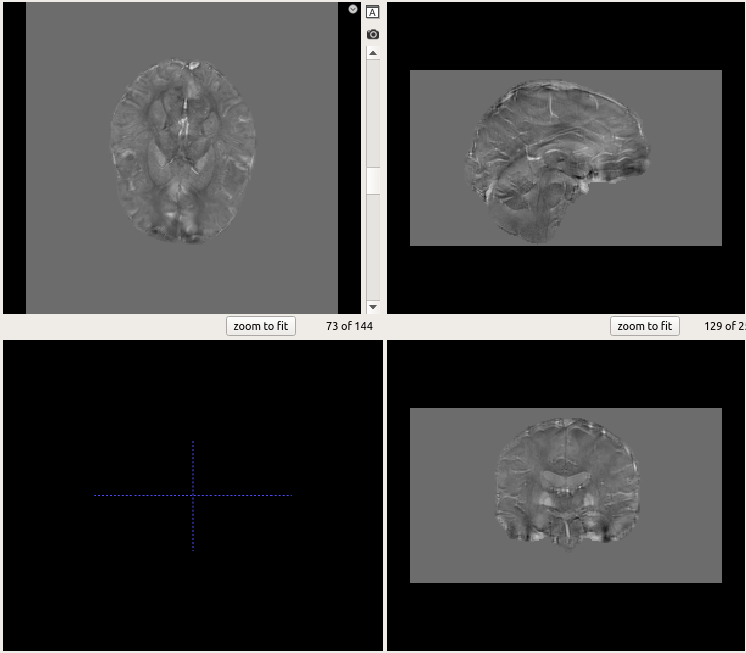

我试图翻转图片1中显示的图像,以匹配图像2的方向,但我不确定如何。

这就是如何以形象为导向: